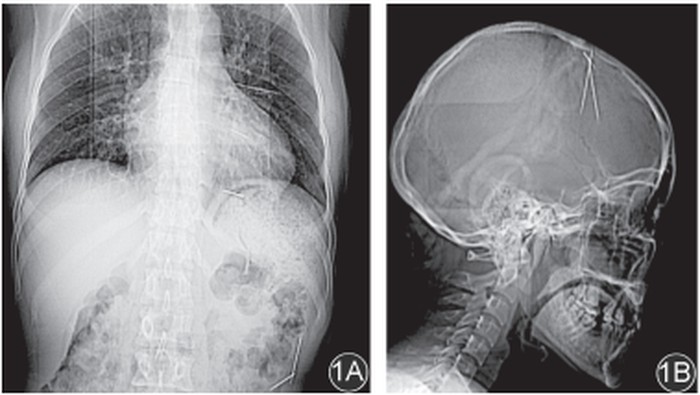

Hasil rontgen yang dilakukan menunjukkan adanya tiga jarum di rongga dada. Pada saat itu, pasien tidak merasakan gejala apapun.

"Karena curiga kemungkinan ada jarum di bagian tubuh lain, kami melanjutkan pemeriksaan rontgen ke bagian tubuh lainnya. Hasilnya, ditemukan tiga jarum di rongga tengkorak (kepala) dan dua jarum di rongga perut," tulis tim dokter dari Departemen Bedah Toraks, Rumah Sakit Tongji, Fakultas Kedokteran Tongji, Universitas Sains dan Teknologi Huazhong, Wuhan, dikutip detikcom, Rabu (5/11/2025).

Setelah itu, tim dokter juga melakukan CT scan untuk mengetahui secara pasti posisi jarum-jarum besi tersebut. Ketika ditanya oleh tim dokter, pasien mengaku tidak mengetahui bagaimana jarum tersebut bisa masuk ke dalam tubuhnya.